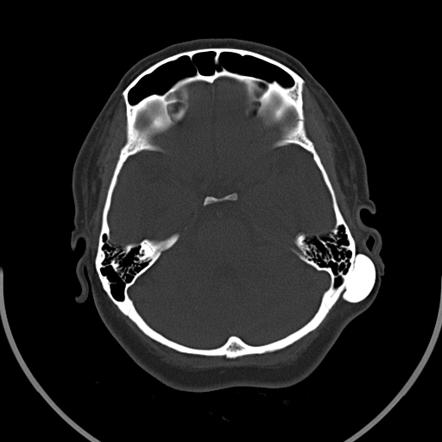

Mastoid Osteoma

This is one of the pictures featuring the Mastoid osteoma. Numerous images associated with the Mastoid osteoma can be utilized as your reference point. Below, you'll find some more pictures related to the Mastoid osteoma.

Title: Figure 1 from a rare case of ivory osteoma of mastoid bone | semantic

Title: Figure 1 from a rare case of ivory osteoma of mastoid bone | semanticFigure 1 from a rare case of ivory osteoma of mastoid bone | semantic.

Title: Mastoid osteoma | radiology case | radiopaedia.org

Title: Mastoid osteoma | radiology case | radiopaedia.orgMastoid osteoma | radiology case | radiopaedia.org.

Title: Axial ct scan. left mastoid cortex osteoma (asterisk) with trabeculae

Title: Axial ct scan. left mastoid cortex osteoma (asterisk) with trabeculaeAxial ct scan. left mastoid cortex osteoma (asterisk) with trabeculae.